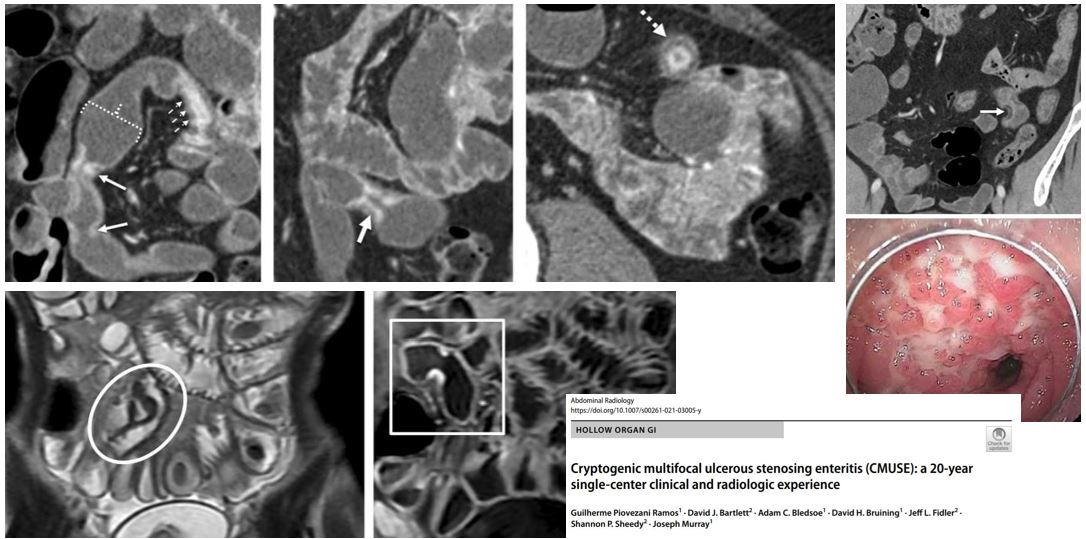

Multifocal, short, ileal strictures with stratified mural hyperenhancement in a patient with iron deficiency anemia? Consider cryptogenic multifocal ulcerous stenosing enteritis (CMUSE) as a cause of occult GI bleeding described by DFP members Jeff Fidler MD and David Bruining